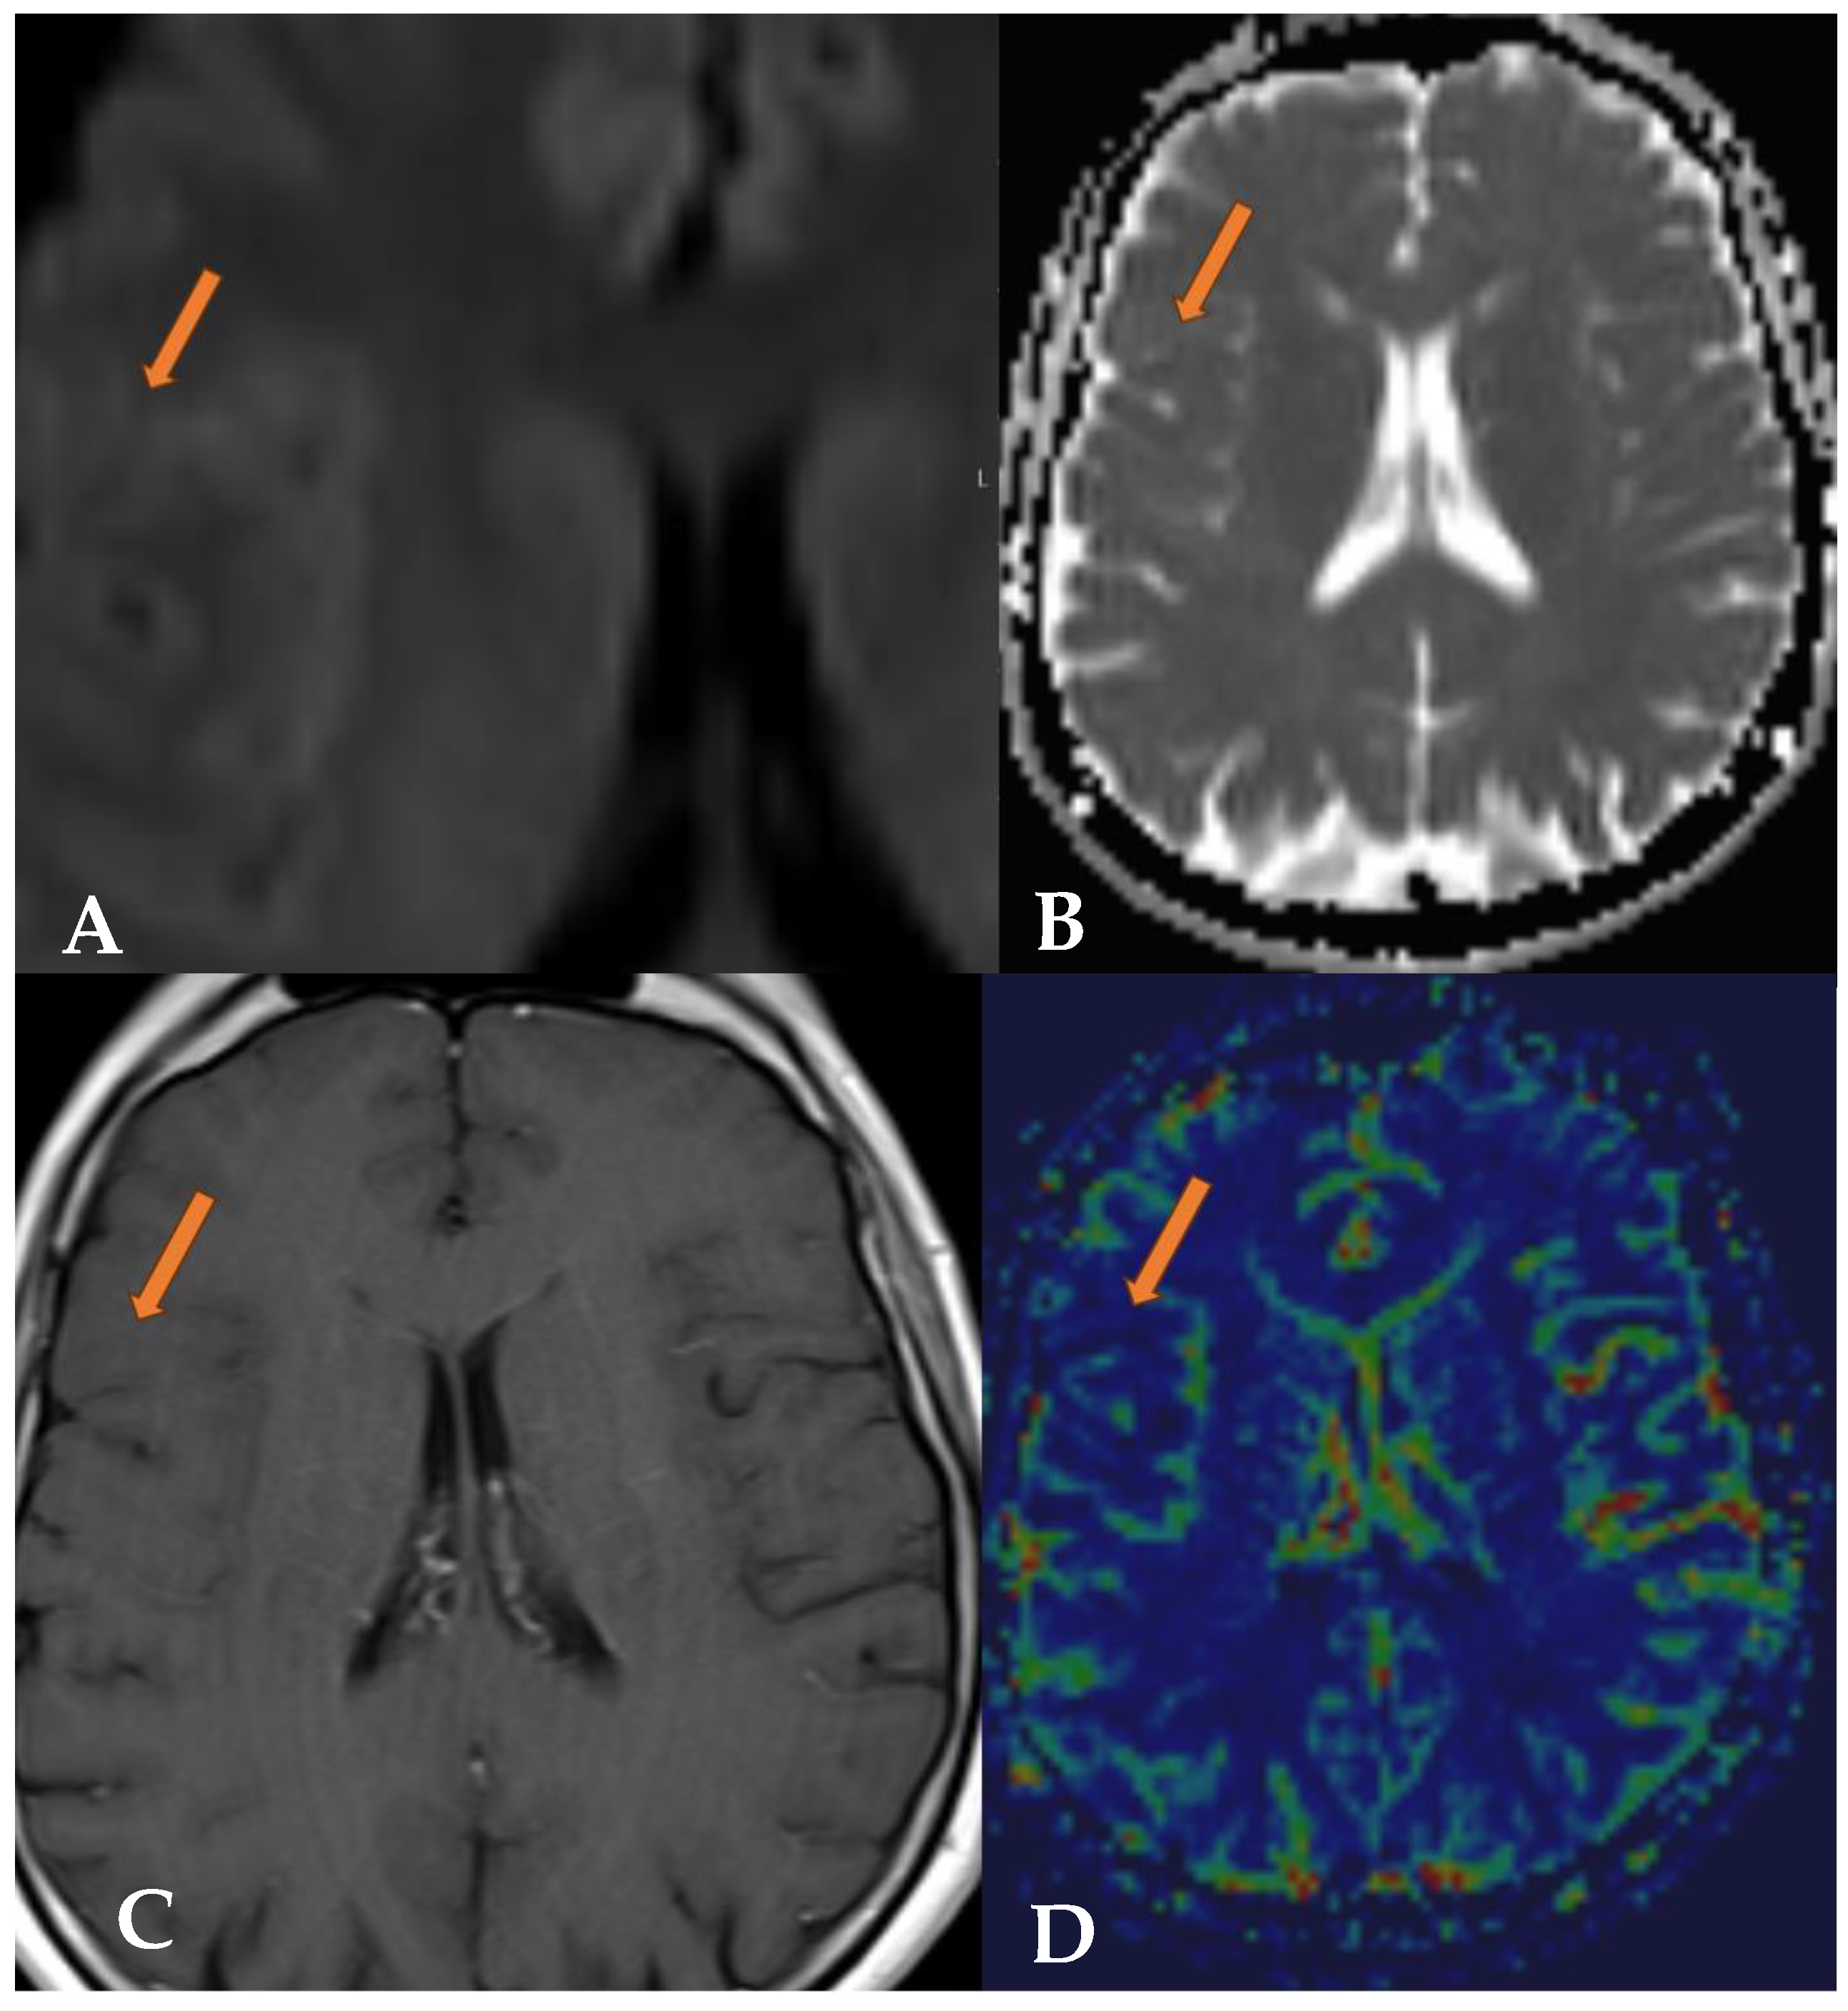

2.1. Case 1

2.2. Case 2